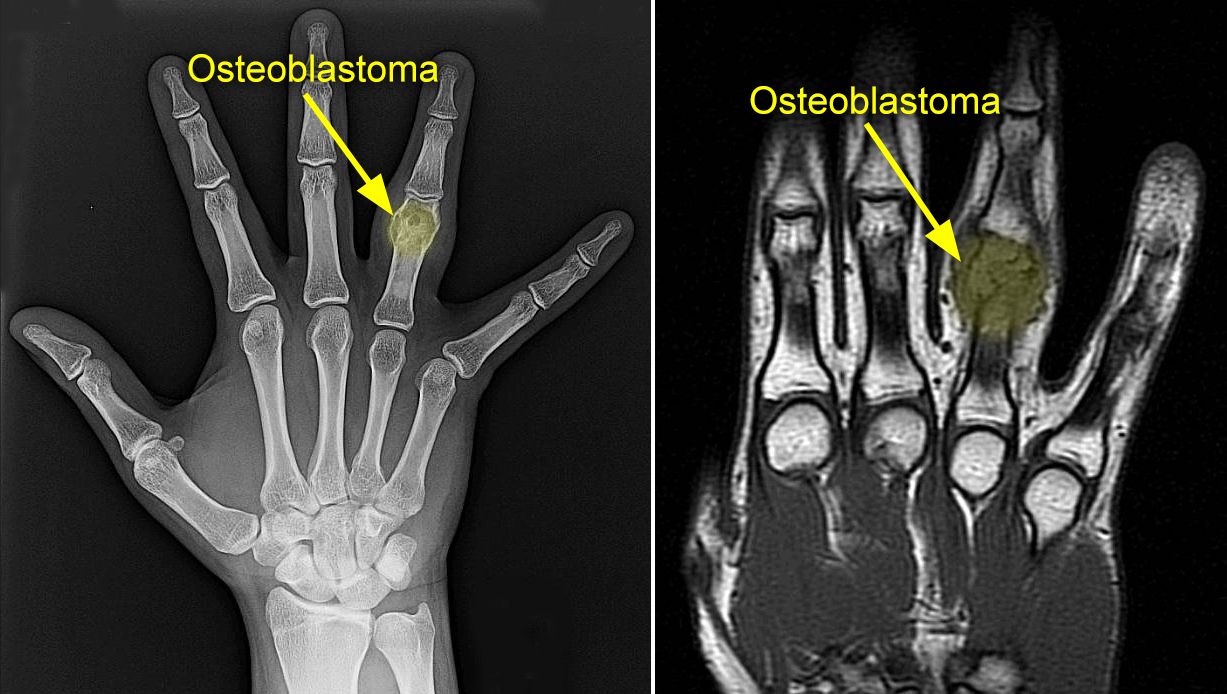

x-ray and mri of osteoblastoma

(Left) An X-ray of an osteoblastoma on a patient's ring finger. (Right) An MRI scan of the same osteoblastoma shows the tumor mass in greater detail.

Other imaging tests. Your doctor may also request computerized tomography (CT) scans, magnetic resonance imaging (MRI) scans, or bone scans to help further define the tumor. These scans can provide more detail, especially of soft tissues. They can also provide cross-sectional images.

A CT scan or MRI scan will show your doctor more precisely where the tumor is located and what its specific characteristics are.